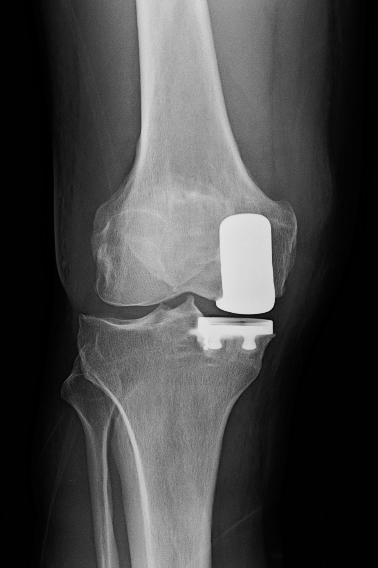

“To qualify for the name, OG Replacement Parts, I needed replacement parts.” His fall also damaged his knees, and he had a partial right knee replacement in the fall of 2021 and then a total ankle replacement (the fifth surgery on the left ankle) in December 2023. “I came up with the name myself, having switched it from Chinbanger, which was created after I flipped over my bike and smacked my chin into a concrete sidewalk.”